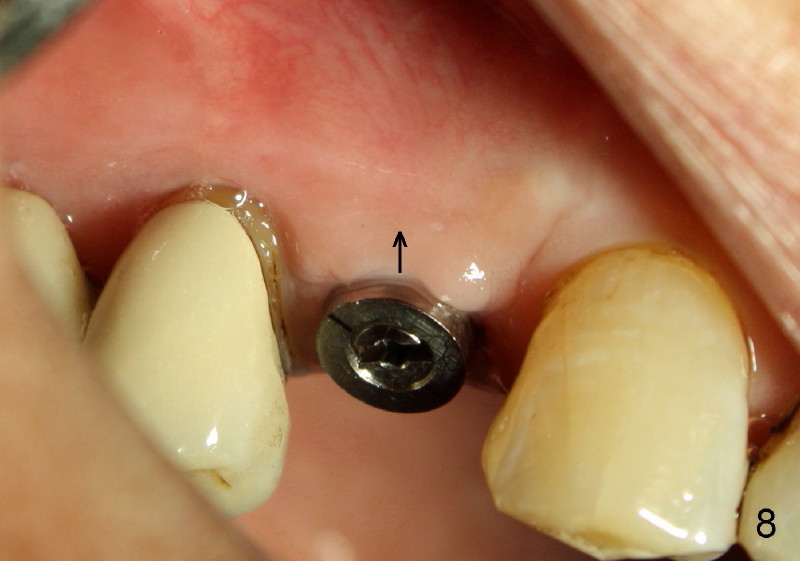

Fig.7-9 are taken 3.5 months postop.  Buccal gingiva appears to have elevated (Fig.8 arrow, as compared to Fig.5 B).  The rough surface seems to have been partially covered by lingual gingiva (Fig.9 arrowheads, as compared to Fig.6).